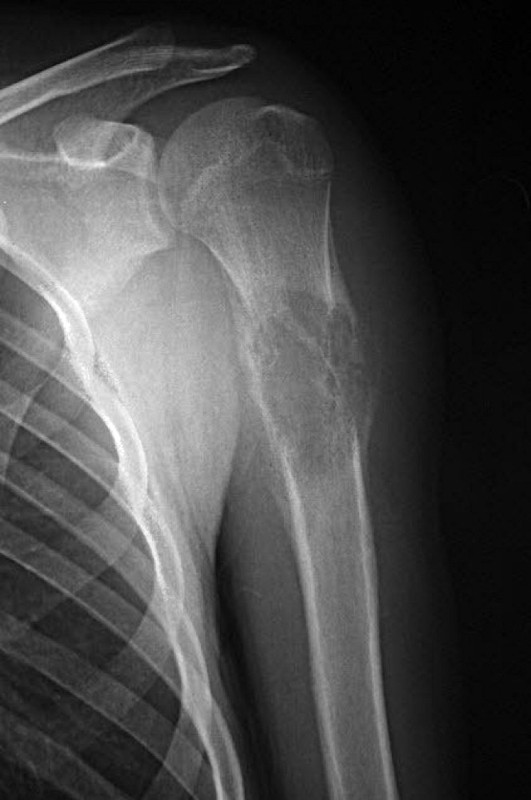

Osteosarcoma

- Descrizione: O sarcoma osteogenico, è il più comune e il più Maligno dei tumori ossei. Colpisce prevalentemente i bambini in età prepuberale e gli adolescenti e la sede prevalente è l'estremità di ossa lunghe, come femore e Tibia, ma anche Omero.

- Foglietto embrionale: Mesoderma recente. Fase di riparazione. Nella Fase attiva si ha una Osteolisi anche di discreta estensione, senza sintomi. Nella fase A della riparazione si ha una edemizzazione cospicua dell'area osteolitica e la tensione sul Periostio causa forte Dolore. La fragilità ossea e elevata e c'è il rischio di Fratture spontanee. Nella fase B si ha dolore, meno intenso, ma che dura a lungo, fino a completa riparazione ossea.